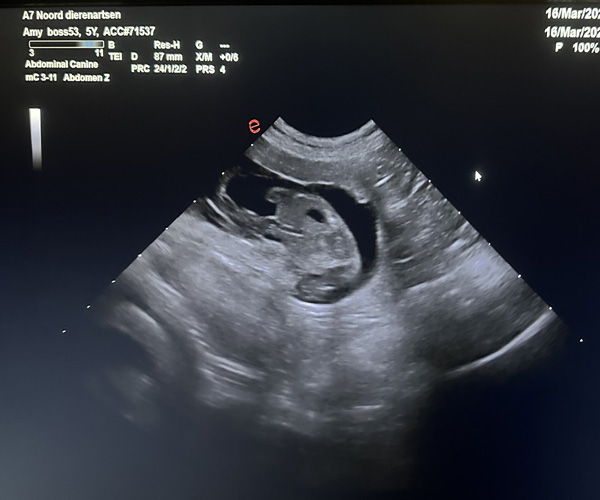

Dinsdag 17 maart: Met heel veel blijdschap delen wij dat onze lieve Amy drachtig is; de echo heeft het bevestigd!

Wij verwachten rond de Paasdagen een prachtig nestje PonDoodle-puppies.

Amy gedroeg zich voorbeeldig bij de dierenarts. Eerst mocht een dierenarts in opleiding de echo doen zodat zij ervaring kon krijgen en daarna deed de dierenarts het nog een keer over. Amy bleef heerlijk rustig liggen en ze genoot van alle aandacht die ze kreeg.